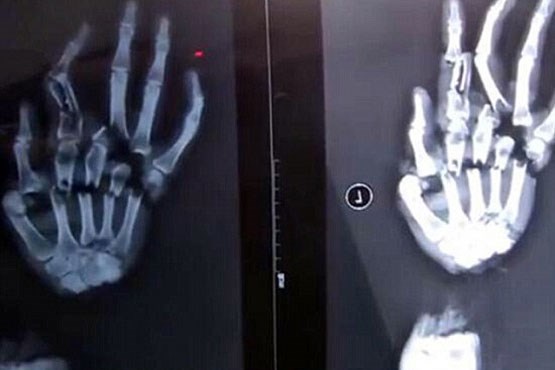

غافل از اینکه همسر خشمگین او را تعقیب کرده است و هنگامی که قربانی می خواست به محل کار وارد شود این مرد بی شرم با ساطور که به همراه داشت همسر خود را مورد حمله قرار داد به طوری که براثر ضربه وارد شده به کف دست او استخوان های انگشتان او خرد شد.

قربانی پس از رسیدن به بیمارستان تحت درمان قرار گرفت.